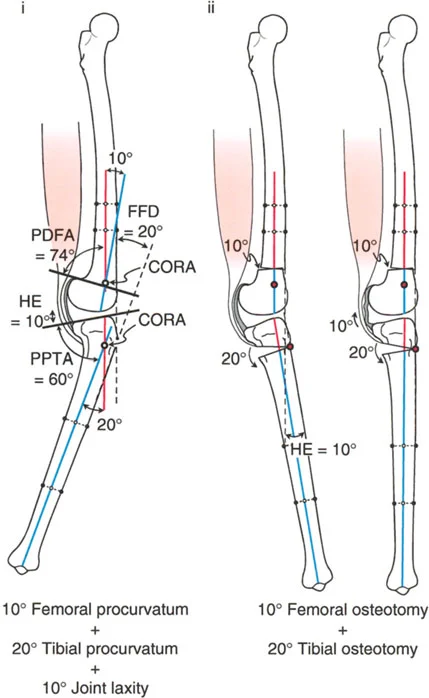

- الأشعة السينية الطويلة للطرف السفلي بالكامل أثناء الوقوف (Standing Long-Leg AP View): تُعد هذه الأشعة حاسمة لتقييم المحاذاة الميكانيكية للطرف السفلي بأكمله. تُظهر بدقة درجة الانحراف الأفحج (Varus) أو الأروح (Valgus) وتساعد في تحديد مركز دوران التشوه (CORA).

- الأشعة الجانبية الطويلة للطرف السفلي بالكامل أثناء الوقوف في أقصى بسط (Standing Long-Leg Lateral View in Maximum Extension): تُستخدم لتقييم تحدد حركة الركبة (FFD) والركبة الارتدادية (Recurvatum)، وتحديد ما إذا كان التشوه عظميًا أو ناتجًا عن تقلص في الأنسجة الرخوة.

تصحيح تحدد حركة الركبة (Flexion Deformity - FFD)

تحدُّد حركة الركبة هو عدم القدرة على مد الركبة بالكامل. يمكن أن يكون سببه عظميًا أو ناتجًا عن تقلص في الأنسجة الرخوة.

- التشخيص الدقيق: يجب تحديد ما إذا كان تحدد الحركة ناتجًا عن تشوه عظمي (تقوس أمامي في الفخذ أو الساق) أو تقلص في الأنسجة الرخوة (الأوتار الخلفية، محفظة المفصل).

- قطع العظم التمديدي (Extension Osteotomy):

- إذا كان التشوه عظميًا، يتم إجراء قطع عظم تمديدي في عظم الفخذ أو الساق لتصحيح التقوس.

- الأستاذ الدكتور محمد هطيف يؤكد على أهمية عدم تصحيح الساق بأكثر من 90 درجة PPTA لتجنب فقدان الميل الخلفي الطبيعي للساق.